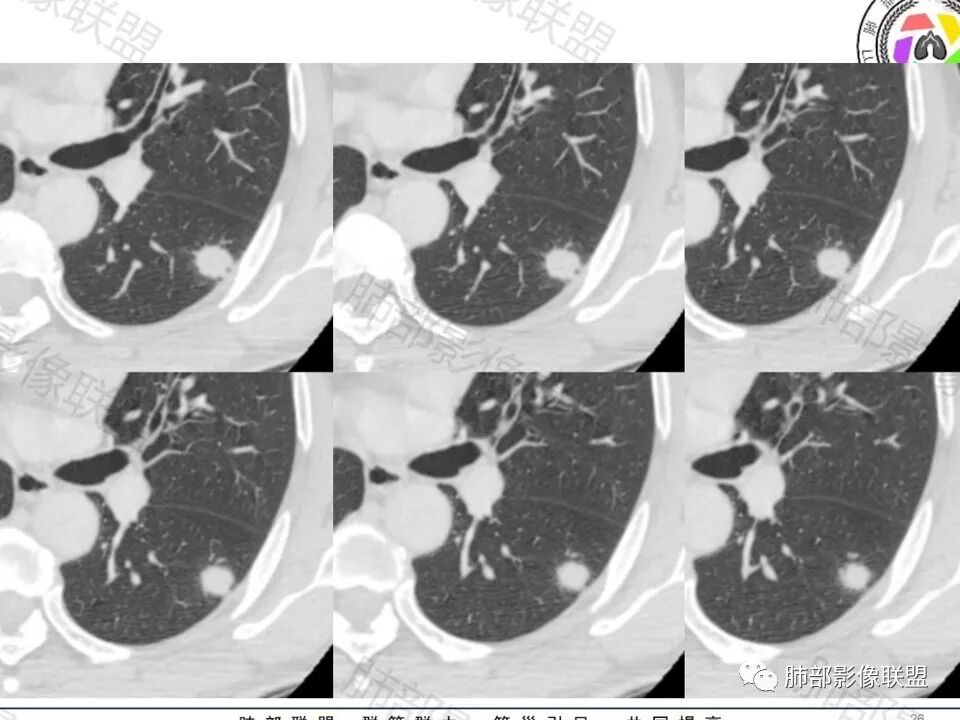

增强的程度很难讲,但是不均匀强化是可以确定的;

有收缩力,但是很轻,按照常理,实性结节因为有占位效应,不太会有收缩力,但是叶间胸膜有凹陷。所以讲,这个结节还是开了放心。

病史:男,60岁,体检左下肺结节,肿标阴性;

影像:轻微肺气肿,可能抽烟;旁边有个卫星灶4-5个,厚层无血管弯,薄层叶间裂轻度增厚,有囊腔,内侧有一个微血管,弯,另有两个微血管直,膨隆,增强血管不弯,糊墙,好像边界有些模糊,17-47-47,冠位轻度叶间裂弯。

诊断:警惕良性,隐球菌感染?

鉴别:腺癌,无磨玻璃,模糊?糊墙;纵膈窗太光滑,胸膜面广;不膨隆。支持点,薄层毛刺,强化。